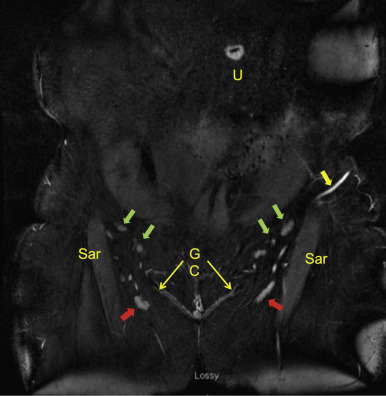

MRA of the donor sites allows the surgeon to select the side with the most favorable lymph nodes and vascular anatomy ( Fig. 8.5 ). This is the side with the largest number and size of lymph nodes, positioned farthest away from the lymph nodes that drain the adjacent extremity. For example, if performing an axillary lymph node transfer, the side with the most abundant lymph nodes located farthest from the axillary vein and its adjacent lymph nodes would likely be a safer and more effective choice. If both sides are equivalent, then the side contralateral to the limb with lymphedema is selected, as this is the preference of most lymphedema therapists. This theoretically allows for clearance of the lymph from the affected limb to adjacent lymph node basins, which would preferably not be harvested.